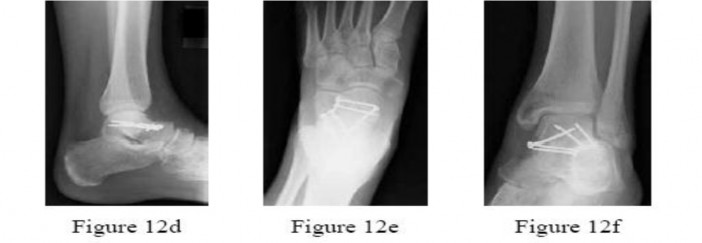

.Figures 12a through 12c show the radiographs of the closed fracture of a 24-year-old man who sustained an isolated injury to his left foot in a motorcycle crash. He was splinted and, on the following day, he nunderwent open reduction and internal fixation. Postoperative radiographs are shown in Figures 12d through 12f. What is the most likely complication of this injury?